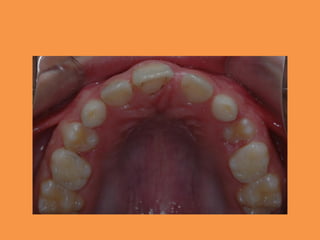

Fig.4a Auxiliary spring design-

constructed with 0.016 × 0.022″ TMA

wire to upright horizontally impacted

maxillary central incisor

Fig.4c Bracket engaged to main

archwire with elastomeric chain

Bracket position correction and

continued alignment

Fig.5 0.016″ NiTi wire engaged in

bracket

Fig.6 0.019 × 0.025″ NiTi wire engaged

in bracket